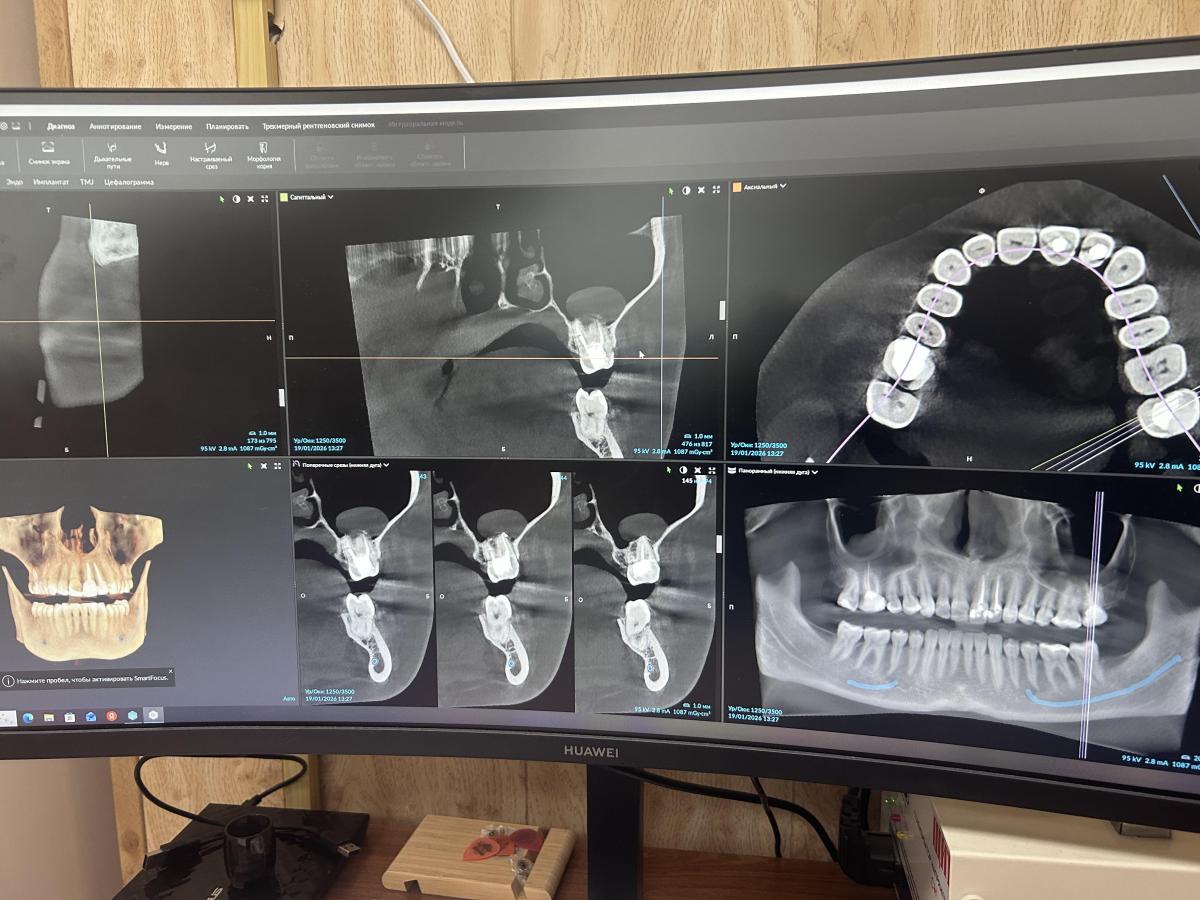

Здравствуйте. Лечила 6 зуб сверху (на снимке где все зубы он сверху слева 3 раза. Крайний раз удаляли нерв, больше не беспокоил где-то год, неделю назад появилась острая реакция на горячее, затем на накусывание и просто языком не дотронуться до него. Сходила к врачу, сделали снимки, сказали зуб пролечен хорошо, кист и прочего нет, только корни расположены близко к пазухам гайморовым из-за этого и болит, сейчас заложена одна ноздря, были боли в шее недели 2 назад очень сильные отдавали в голову, зуб при этом не болел. Скажите, пожалуйста, если по этим снимкам что-то видно, действительно ли зуб вылечен нормально?

kristinanana, на таких скринах диагноз невозможен!